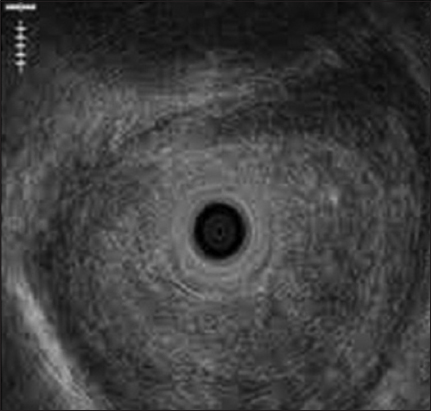

The mean length of benign and malignant esophageal strictures was 2.4±1.1 cm and 5.3±1.6 cm, respectively (P=0.0003). The esophageal wall stratification was lost in all the patients with malignant strictures (Fig. 1-3) but in only 3/10 (30%) patients with benign strictures (P=0.03). The mean esophageal wall thickness in patients with malignant strictures was 11.7±2.5 mm, significantly greater than in those with benign strictures (7.1±2.2 mm; P=0.0005). The loss of wall stratification on EUS had a sensitivity, specificity, negative and positive predictive values of 100%, 70%, 100% and 75%, respectively for the diagnosis of malignancy, whereas a wall thickness of 9 mm or more on EUS had a sensitivity, specificity, and accuracy of 78%, 80%, and 79%, respectively, for the diagnosis of malignancy.

Figure 1 Preserved wall stratification with mucosal thickness in patient with peptic stricture